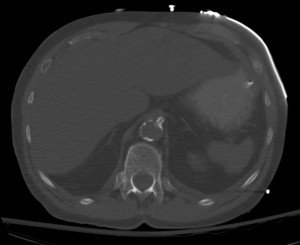

Celiac stent for mesenteric ischemia

Celiac artery stent as seen on axial image of CT